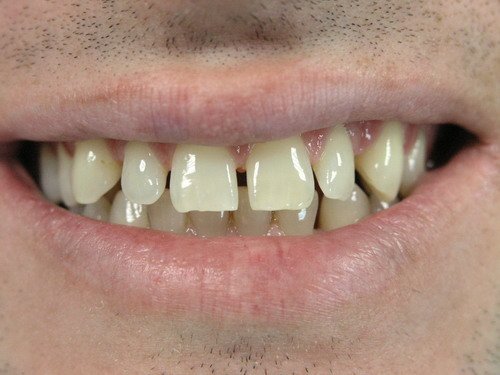

Какви са процедурите за избелване на зъбите при изложен емайл и проблеми с венците?

Какви са цените на порцелановите фасети и коронките в България?

Каква е разликата между металокерамиката и порцелановите фасети?

Какви са процедурите за избелване на зъбите при изложен емайл и проблеми с венците?

При изложен емайл и проблеми с венците, избелването на зъбите може да бъде рисковано. В тези случаи е важно да се консултирате със зъболекар, който може да прецени дали избелването е подходящо за вас. За пациенти с проблемни венци, избелването може да се направи и със зъбни 'светулки', които се залепват със специален цимент.

Какви са цените на порцелановите фасети и коронките в България?

Цените на порцелановите фасети варират, но обикновено се движат между 300 и 700 лв. на зъб. Важно е да се отбележи, че цената може да варира в зависимост от различни фактори като качеството на материалите, професионализма на зъболекаря и зъботехника, както и избраната лаборатория. Цените на короните и фасетите в България могат да варират в различните стоматологични кабинети. Например, в един кабинет цената на керамичните корони и фасети може да бъде 450лв, докато в друг може да бъде различна. Цената за лечение на даден пациент се определя след преглед и евентуални лабораторни изследвания, преди да е започнало лечението.

Каква е разликата между металокерамиката и порцелановите фасети?

Металокерамиката е конструкция, която включва метална основа, покрита с керамичен слой. За разлика от тях, порцелановите фасети са тънки порцеланови облицовки, които се поставят върху съществуващите зъби. Важно е да се отбележи, че порцелановите фасети предлагат по-естествен външен вид и са по-дълготрайни от металокерамиката.